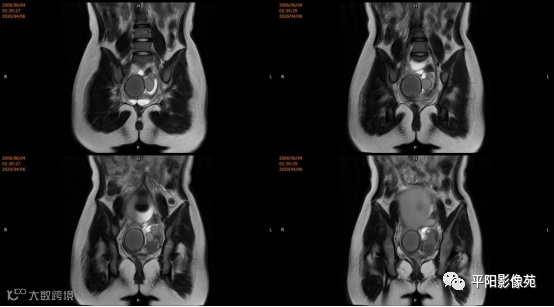

子宫10cm×12cm大小,饱满,呈紫红色,子宫下段增粗膨大呈柱状,右侧卵巢可见一约18*15cm大小的肿物,表面呈紫红色,输卵管明显增粗膨大,伞端及卵巢粘连包裹于子宫后壁及侧盆壁,左侧卵巢可见一约8*7cm大小的囊肿,左侧输卵管增粗膨大伞端包裹粘连于子宫后壁及侧盆壁,直肠粘膜粘连于子宫后壁。部分大网膜粘连于子宫及卵巢表面。 注射器针头刺入子宫肌层至宫腔,抽取出大量暗红色血液,宫腔内积血,子宫缩小,子宫下段膨大,不排除生殖道畸形,双侧卵巢巧克力囊肿可能,钝性分离粘连,针头刺入右侧卵巢囊腔,吸出咖色液体约800ml,娩出右侧卵巢,切开右侧卵巢囊肿表面组织达囊壁,钝性剥离囊肿,剥离过程中可见大量黑褐色液体流出,3-0可吸收线缝合囊腔止血使卵巢成形,大小约5*6cm,同法处理左侧,使左卵巢成形,分离双侧输卵管粘连,暴露伞端,行宫腔穿刺可抽取出大量暗红色血液,考虑生殖道畸形,需改阴式手术探查,破坏处女膜,术中向患者家属交待病情,需改阴式手术破坏处女膜,患者家属表示理解,同意改阴式探查并签字。 患者取膀胱截石位,常规消毒铺巾,见外阴外观发育正常,分开小阴唇,见尿道口下方可见处女膜环,剪开处女膜环,可见阴道壁约1cm,前为盲端,分开处女膜后,于尿道下方阴道口位置,将1:10000的肾上腺素注入阴道直肠间隙,在尿道口下方阴道壁痕迹处横切约2.5cm,钝性分离,可及一囊肿,表面淡紫色,20ml注射器经此处穿刺,抽出暗褐色积血,用注射器向阴道积血方向穿刺,抽出褐色积血,探查囊腔与宫腔相通,未见明显宫颈组织,上段未见阴道粘膜,考虑宫颈缺如及生殖道畸形,清理宫腔积血,将子宫下段最低端缝合于约1cm的阴道粘膜上,形成宫颈形状,宫腔放置一根引流管,查无出血。

无痛宫腔镜检查:可见手术缝扎线,未见宫颈组织,宫腔形态失常,可见子宫内膜,未见明显双侧输卵管开口。

宫颈缺如、阴道闭锁

4.MRI检查 对软组织分辨率好,能够清晰区分子宫及阴道,对子宫内膜、结合带、肌层可清晰分辨;能明确子宫、宫颈、阴道结构异常的部位、范围、性质等。宫腔内经血潴留时,宫腔内见短T1长T2信号。